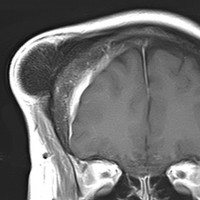

大脳鎌テント接合部髄膜腫 falcotentorial meningioma

30代の女性に発生した髄膜腫です,一見すると松果体細胞腫と見分けはつきません。右の画像に見られるように典型的な中脳水道狭窄を生じていました。

軽度の閉塞性水頭症もありますが,頭痛も無く無症状なので経過を観察しました。髄膜腫だと診断できるのは,右の画像で見られるようにガレン大静脈が右側に偏っているからです。松果体細胞腫の場合は,ガレン大静脈は上方に変位します。

1年間経過観察したら水頭症が進行して脳室が拡大,腫瘍のサイズも大きくなりました。右側の画像で見られるようにガレン大静脈の左側のテントの下面から発生した髄膜腫でした。

左は手術直後の画像です,手術は左側のテント下面を見るために,後頭部経テント法 OTA occipital transtentorial approach で,小脳テントの左側を切断して腫瘍を全摘出しました。右側は6年後の画像ですが,腫瘍再発はありません。

「注意」症状のない患者さんには,なかなか勧められないリスクの高い手術です。この患者さんの場合は無症状で水頭症も軽度で経過観察をしたのですが,本当はそうしてはならないものでした。閉塞性水頭症が急激に悪化して,急性水頭症のために意識障害になる可能性があるものです。